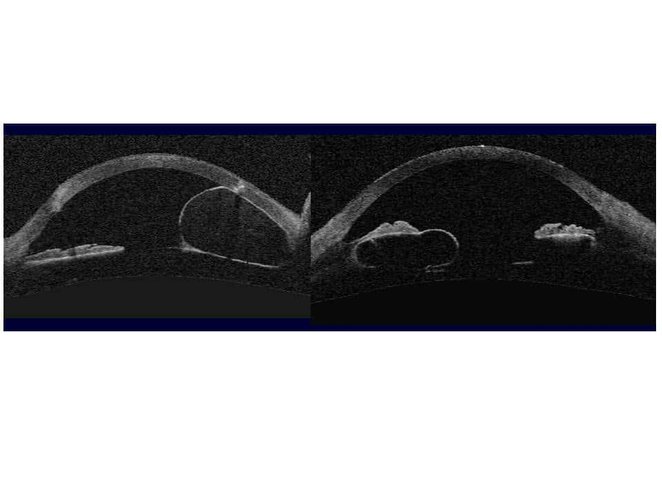

Volumineux kyste iriens, à la fois développés aux dépends du stroma irien (cliché de gauche) et de l’épithélium pigmenté irien (cliché de droite), et entrainant une fermeture localisée de l’angle irido-cornéen avec apposition de l’iris contre la trabéculum et l’endothélium cornéen.

(Cliché dû à l’amabilité de Aptel F, Grenoble).